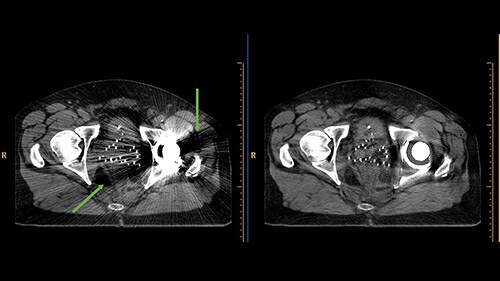

Metal artifacts in CT images, manifesting as dark streaks (green arrows). O-MAR enhances the visualization of structures by iteratively calculating interpolated values which simulate tissue.

With O-MAR, not only are severe streaking artifacts reduced, substantial portions of previously obscured anatomy can now be visualized. Since the system will always reconstruct both sets of images whenever O-MAR is selected, the uncorrected images are readily available. Although the main purpose of O-MAR is to address artifacts arising from orthopedic metal, it is also effective for some kinds of non-orthopedic metal, e.g. dental fillings.